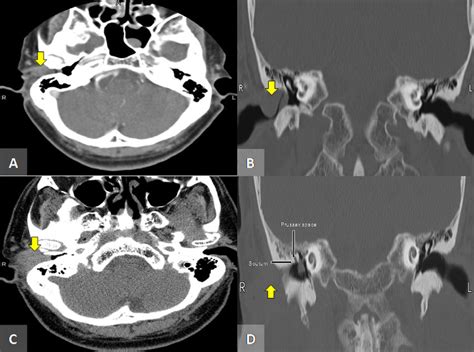

- Internal Acoustic Meatus